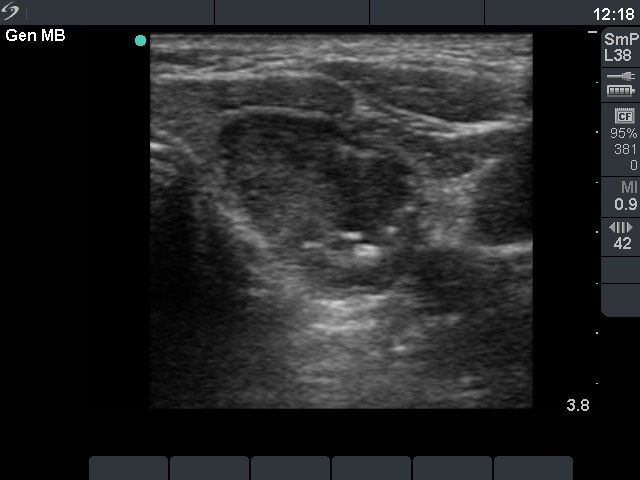

Benign cystic-colloid goiter (cytological diagnosis) - case 123 |

Intrathyroidal parathyroid adenoma (histological diagnosis) - case 1399 |

The synchronous presence of hyperechogenic lines and granules proves that these figures represent connective tissue while one in the ventral part does represent a colloid crystal.

There are a few hyperechogenic granules within the small lesion and we can see two much thinner lines, as well. These figures might be either punctate echogenic foci or non-specific granules of a normal connective tissue.